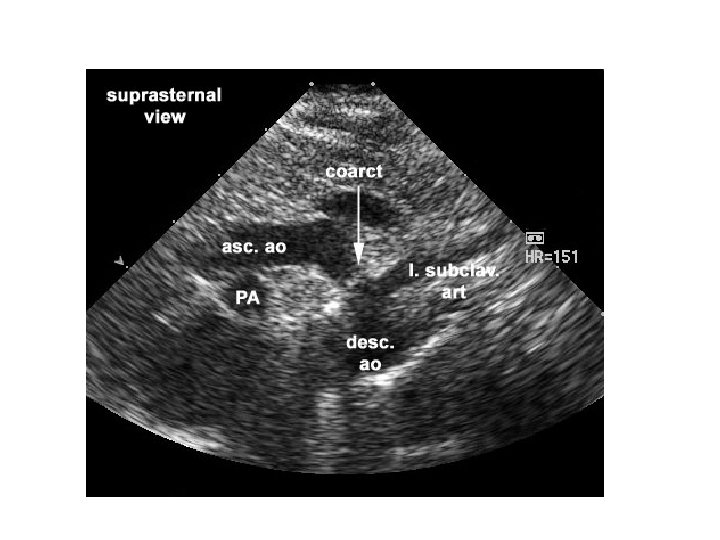

The target diagnosis • Critical congenital heart disease (CCHD) • CHD which is duct dependant and may cause sudden severe illness after PDA closure, and CHD which requires surgery in the 1 st 28 days of life • Includes most cyanotic CHD, and left heart obstructive lesions

False negatives • 17% of infants with CCHD which was not diagnosed antenatally will still be discharged without diagnosis • Mostly Coarctations, IAA occasionally others (TGA…) • Must be sure that parents know (just as with other screens) that a negative screen is not 100%, and babies still need normal health care